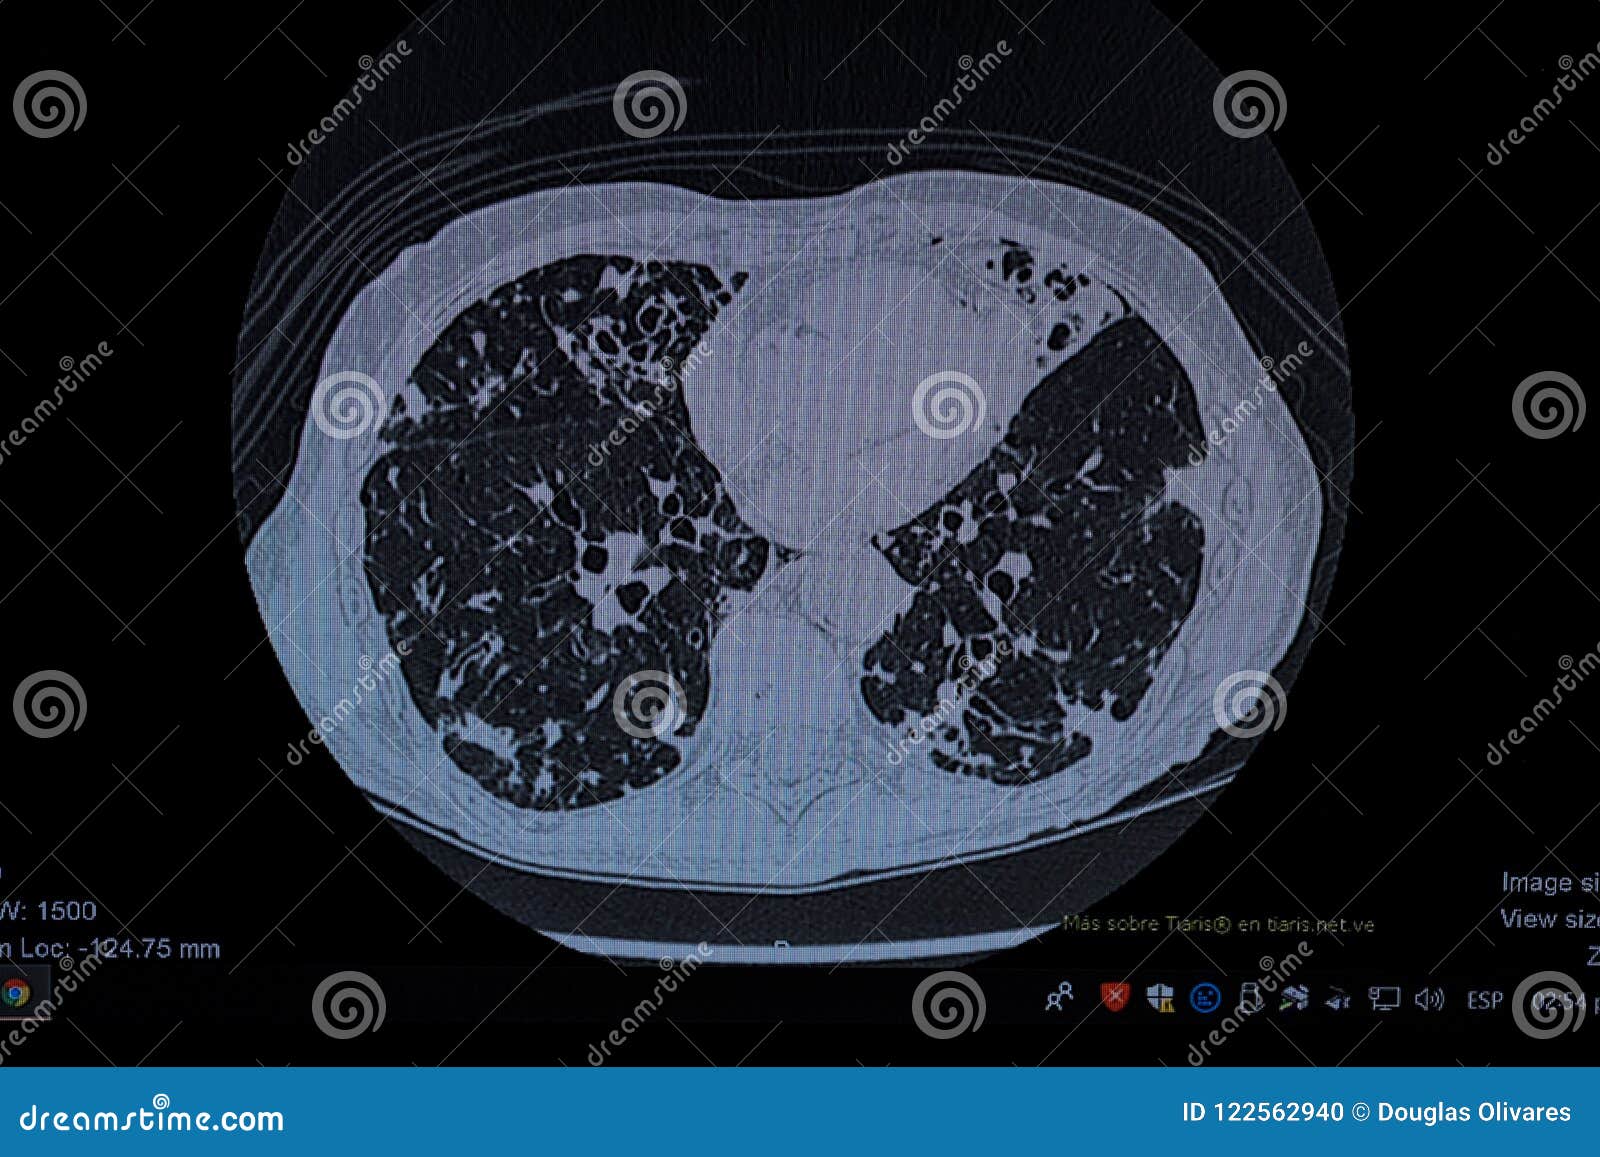

Cystic Bronchiectasis on Chest Xray X Rays Case Studies CTisus CT Bronchiectasis Chest X Ray Images bronchiectasis is defined as irreversible dilatation of a portion of the bronchial tree. Hover on/off image to show/hide findings. A bronchiectatic airway can show abnormal widening and thickening of its airway wall. diagnosis of bronchiectasis is usually made using chest computed tomography (ct) scan, the current gold standard method. the diagnosis of bronchiectasis requires the presence of. Bronchiectasis Chest X Ray Images.

Chest Xray and CT scan showing bronchiectasis with airfluid levels Bronchiectasis Chest X Ray Images diagnosis of bronchiectasis is usually made using chest computed tomography (ct) scan, the current gold standard method. the diagnosis of bronchiectasis requires the presence of clinical symptoms as well as characteristic radiographic features on. Chest radiograph in a patient with severe. Hover on/off image to show/hide findings. The three most important mechanisms. bronchiectasis is defined as irreversible. Bronchiectasis Chest X Ray Images.